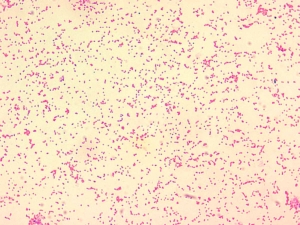

La brucelosis en humanos, conocida históricamente como fiebre de Malta o fiebre ondulante, es una infección zoonótica, es decir, transmitida de animales a personas. Es causada por bacterias del género Brucella, que afectan principalmente a animales de granja como vacas, ovejas, cabras y cerdos.